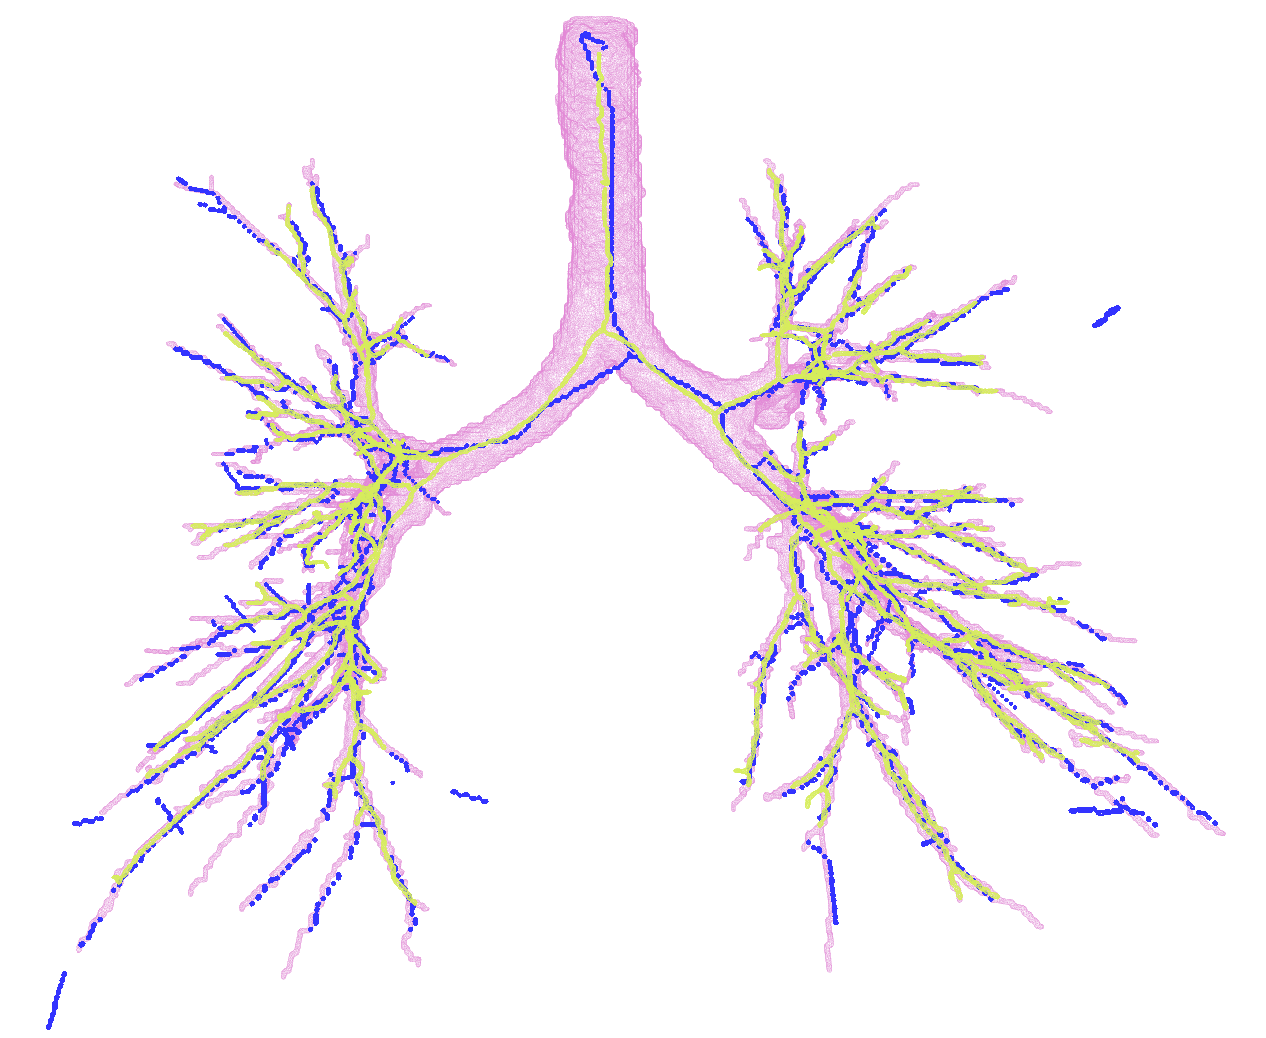

In Figure 2, first we present the predicted subgraph for one of the images. The gray dots are nodes of the over-complete graph with features, , extracted using Bayesian smoothing; the edges are colour-coded providing an insight into the performance of the method: yellow edges are true positives, red edges are false positives and blue edges are false negatives compared to the ground truth connectivity derived from the reference segmentations. Several of the false negatives are spaced closely, and in fact, do not contribute to the false negative error, , after generating the binary segmentations. The figure to the right in Figure 2 shows four predicted centerlines overlaid with the reference segmentation and centerlines from the voxel-classifier approach. Clearly, the MFN method is able to detect more branches as seen in most of the branch ends, which is also captured as the reduction in in Table 1. Some of the false positive predictions from MFN method appear to be a missing branch in the reference as seen in the first of the four scans. However, there are few other false positive predictions that could be due to the model using only pairwise potentials; this can be alleviated either by using higher order neighbourhood information or with basic post-processing. The centerlines extracted from MFN are slightly offset from the center of airways at larger scales; this could be due to the sparsity of the nodes at those scales and can be overcome by increasing resolution of the input graph.